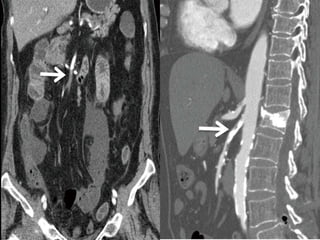

Sagittal subvolume and coronal subvolume MIP images show severe stenosis of

the celiac, superior mesenteric and inferior mesenteric arteries.

Sagittal subvolume andcoronal subvolume MIP images show severe stenosis of the celiac, superior mesenteric and inferior mesenteric arteries.